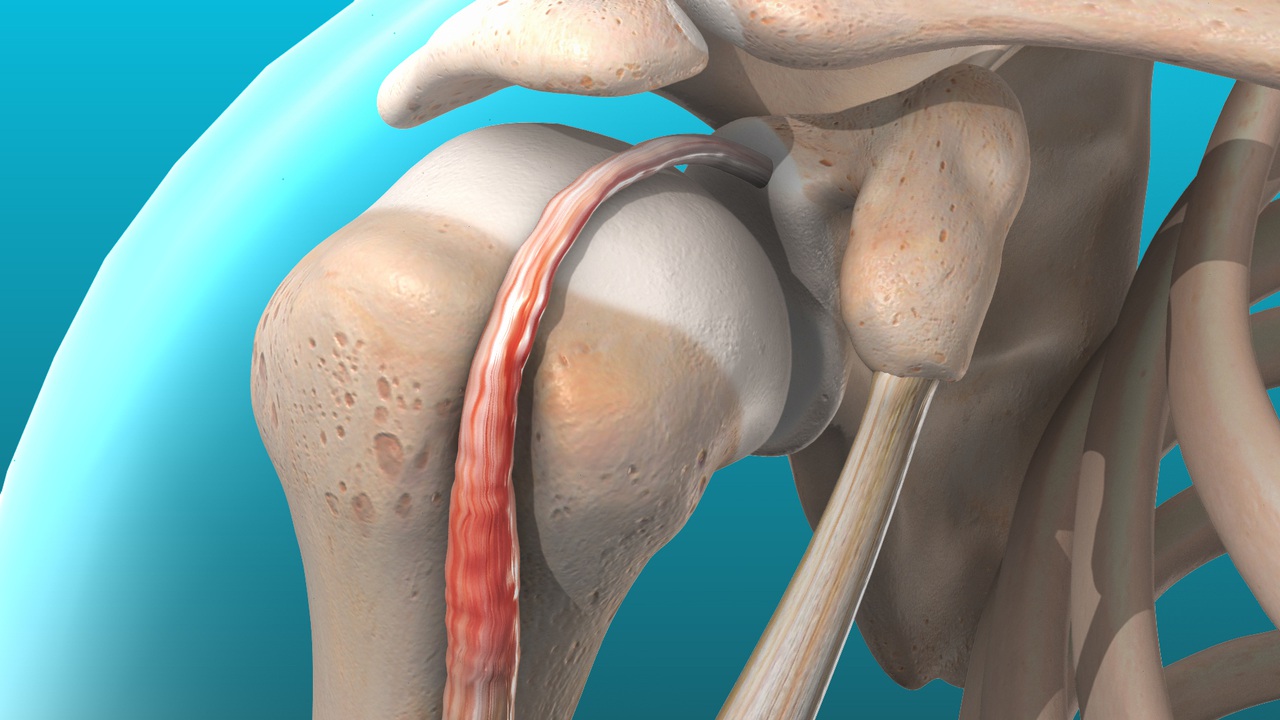

Diagnose this injury. Provide Moi, signs and symptomsand management

glenohumeral disclocation

moi - anterior = abduction , external rotation and extension, inferior, posterior = abduction, internal rotation

signs and symptoms = flattened deltoid contour, inability to move arm, moderate - severe pain, nerve involvement - numbness/ tingling

management - do not relocate - damage to nerve and blood vessels, immobilise with sling, police, refer to medical professional to relocate, use protective gear /braces , restore ROM, stregthen, prevent reoccurence